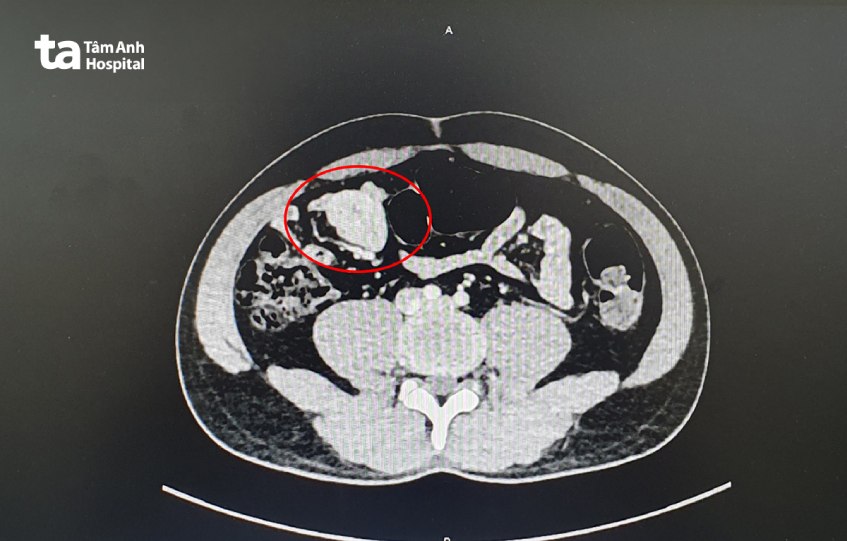

Người bệnh ngụ Cần Thơ, đến Bệnh viện Đa khoa Tâm Anh TP HCM khám nam khoa do đau vùng sinh dục. Bác sĩ chỉ định chụp CT scan, kết quả cho thấy khối u kích thước lớn nằm ở mạc treo ruột non. Tuy nhiên, người bệnh không cảm thấy đau bụng, buồn nôn, không sốt, tiêu tiểu bình thường.

Thạc sĩ, Bác sĩ CKII Trần Hiếu Nhân, Trung tâm Nội soi và Phẫu thuật Nội soi Tiêu hóa, tư vấn người bệnh phẫu thuật nội soi lấy u, phòng trường hợp khối u có thể tăng kích thước dẫn đến biến chứng nguy hiểm chèn ép lên các tạng xung quanh, không loại trừ khả năng ung thư.

Sau 30 phút phẫu thuật, bác sĩ loại bỏ toàn bộ khối u kích thước 3 cm, không làm tổn thương mạch máu ruột. Người bệnh hồi phục nhanh, xuất viện sau hai ngày. Kết quả giải phẫu cho thấy anh Thanh mắc bệnh Castleman, tức tăng sản nang lympho – mạch máu và tăng sản hạch bạch huyết khổng lồ lành tính. Đây là một dạng rối loạn liên quan đến sự sinh sản quá mức của các tế bào trong hạch bạch huyết, có thể gặp ở bất cứ vùng hạch nào. Người bệnh cần tái khám định kỳ, siêu âm mỗi 6 tháng một lần.